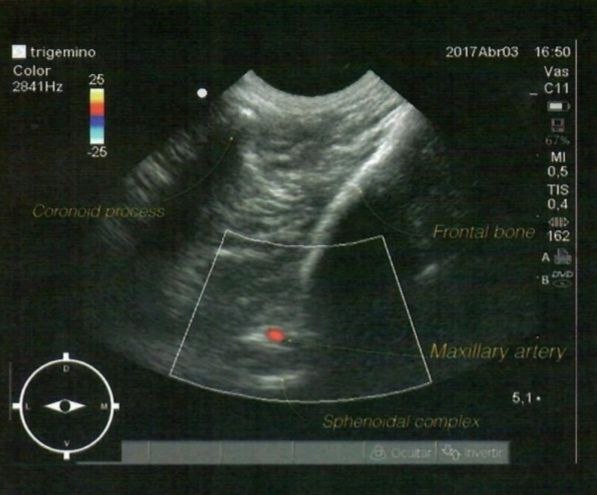

Тройничный нерв (trigeminal n.) обеспечивает сенсорную иннервацию областей, иннервируемых верхнечелюстным, нижнечелюстным и глазным нервами (в частности, лицевой отдел черепа, зубы, язык), а также иннервирует твердую мозговую оболочку6,7. Преимуществом применения блокады тройничного нерва является значительная площадь десенсибилизации: с помощью одной инъекции можно достичь анальгезии обширной зоны, охватывающей половину головы (рис. 17, 18). Процедура требует использования ультразвуковой навигации для визуализации сосудов и костных структур, что позволяет минимизировать риски и повысить точность проведения манипуляции (рис. 19, 21, 22)6.Техника проведения. Пальпаторно определяются анатомические ориентиры – скуловой отросток лобной кости, скуловая дуга и крылонёбная ямка. Место пункции – точка, располагающаяся в крылонёбной ямке каудально от скулового отростка лобной кости. УЗ-датчик размещается в височной области непосредственно за связкой орбиты; необходимо визуализировать каудальную часть крылонёбной ямки, латеральную часть лобной кости и крылонёбный узел (ганглий). После определения акустического окна необходимо активировать режим цветного доплера и определить верхнечелюстную артерию, которая выходит из крыловидного канала. Далее игла вводится параллельно датчику от медиальной плоскости в латеральном направлении, пока ее кончик не окажется около верхнечелюстной артерии; после проведения аспирационной пробы местный анестетик вводится выше и ниже местонахождения артерии6.

Frontal bone – лобная кость. Maxillary artery – верхнечелюстная артерия.